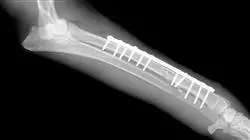

تثبيت الكسر الخارجي هو استخدام دليل جامد يقع خارج الجسم ومتصل بالعظم بواسطة إبر تخترق الجلد (عبر الجلد). تُظهر تقنية التثبيت مقارنة بطرق التثبيت الداخلي الأخرى أن التثبيت الخارجي يحسن البيئة البيولوجية، ويحافظ على الأنسجة الرخوة وإمدادات الدم، ويسرع الشفاء، ويقلل من خطر العدوى، ويقلل من وقت الجراحة.

يوفر المثبت الخارجي تثبيتًا مستقرًا لنهايات العظام دون الحاجة إلى غرسات عند خط الكسر أو تثبيت المفاصل المجاورة، لذلك فهو موصى به بشكل خاص للكسور المفتوحة أو المكشوفة أو المصابة. يسمح بضغط أطراف العظام أو تحييدها أو تشتيت انتباهها حسب حاجة علم الأمراض.

بدأ تثبيت الكسور باستخدام المسامير داخل النخاع (IM) في الكلاب والقطط في ال 40. ازدادت شعبيتها بسبب التقدم في التخدير،وتقنيات التعقيم،والمضادات الحيوية،ووعي الأطباء البيطريين ومالكي الحيوانات أنه في معظم الحالات المعالجة،كان هناك إصلاح مُرضِ.

لذلك، لطالما كان المسمار داخل النخاع هو الزرع الأكثر استخداماً في الطب البيطري لأنه يوضع في قناة النخاع ومقاوم للانحناء في جميع الاتجاهات. ترتبط قوتها بقطرها وقدرتها على تقييد حركة شظايا العظام المكسورة. إنه نظام التثبيت الأكثر استخدامًا في الكلاب والقطط.

من جهة أخرى، في ال 20 عاماً الماضية، تطور تثبيت الكسور بشكل هائل باستخدام غرسات تثبيت داخلية صلبة، مثل الصفائح. يمكن للمرء أن يتحدث عن ثمانية أو تسعة أنظمة تثبيت مختلفة للكسور عن طريق الصفائح. في هذه الحالة، التخصص سيركز على الأكثر استخداماً في جميع أنحاء العالم.